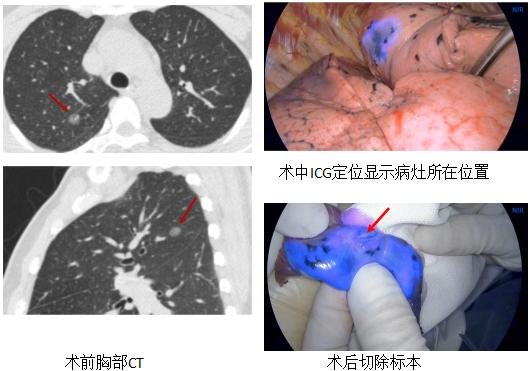

ENB引导下注射ICG胸腔镜术前肺微小病变定位